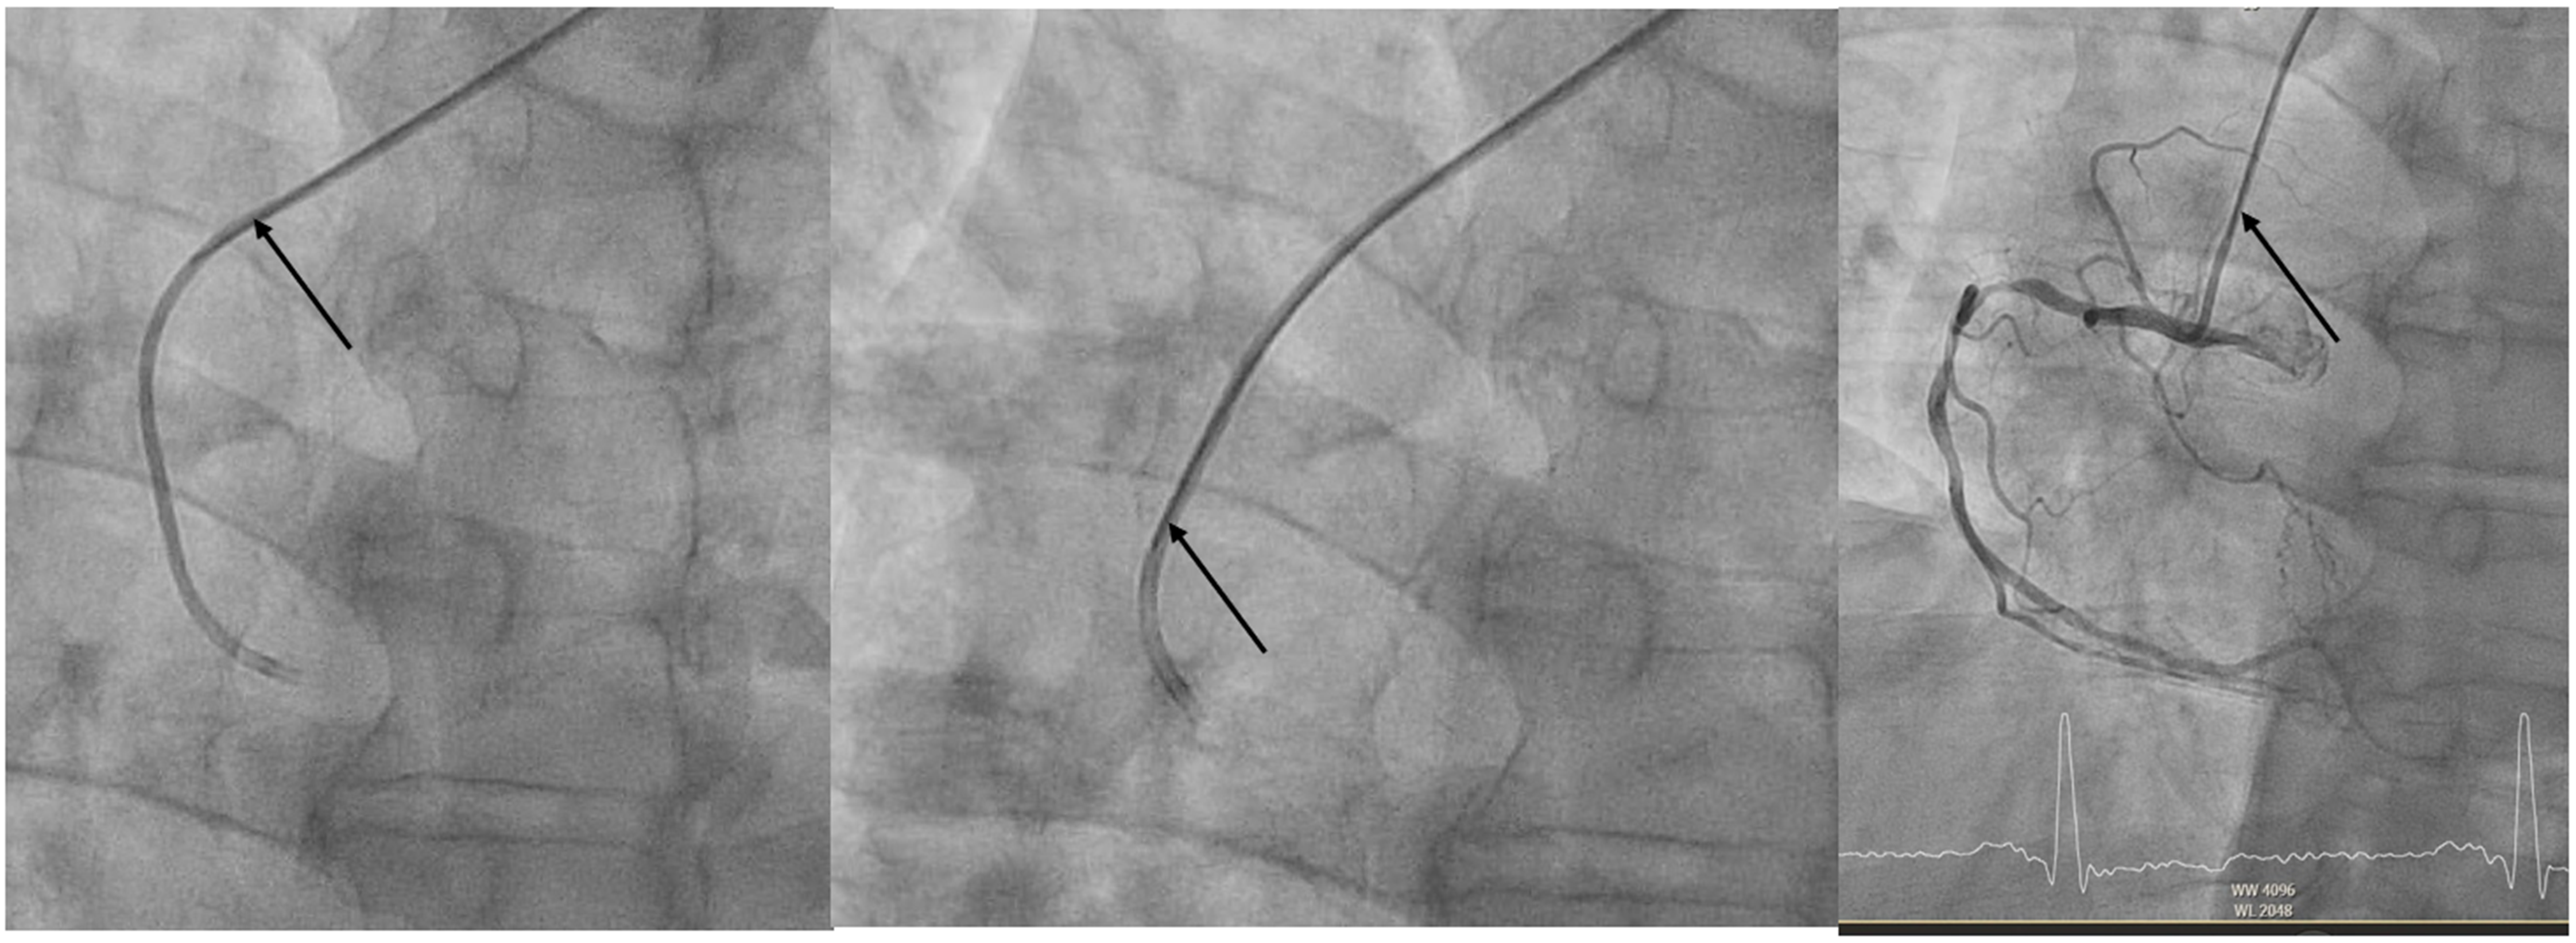

Following left coronary injections, the stiff wire is advanced so that its rigid segment extends just beyond the first curve of the catheter, straightening it into a shape mimicking a JR4 or multipurpose configuration (Figure 1). The wire is left in place during RCA injections to maintain support and coaxial alignment (Figure 2). Notably, the residual lumen of a 5F guiding catheter with a 0.032-inch wire in place (~1.06 mm²) exceeds that of a standard 5F diagnostic catheter (~0.95 mm²), ensuring safe and effective contrast delivery (Figure 3).